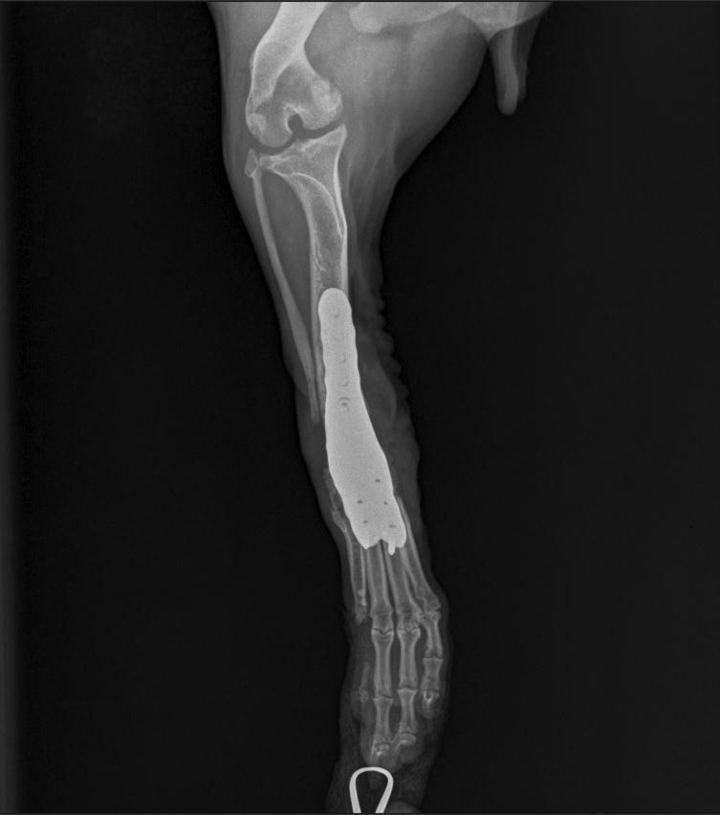

В итоге, 30 октября врачи прооперировали Митю. Операция прошла без осложнений.

- Установили имплант, – говорит Юлия. - Как сказал врач, уже на третий день после операции собака должна встать на лапу.